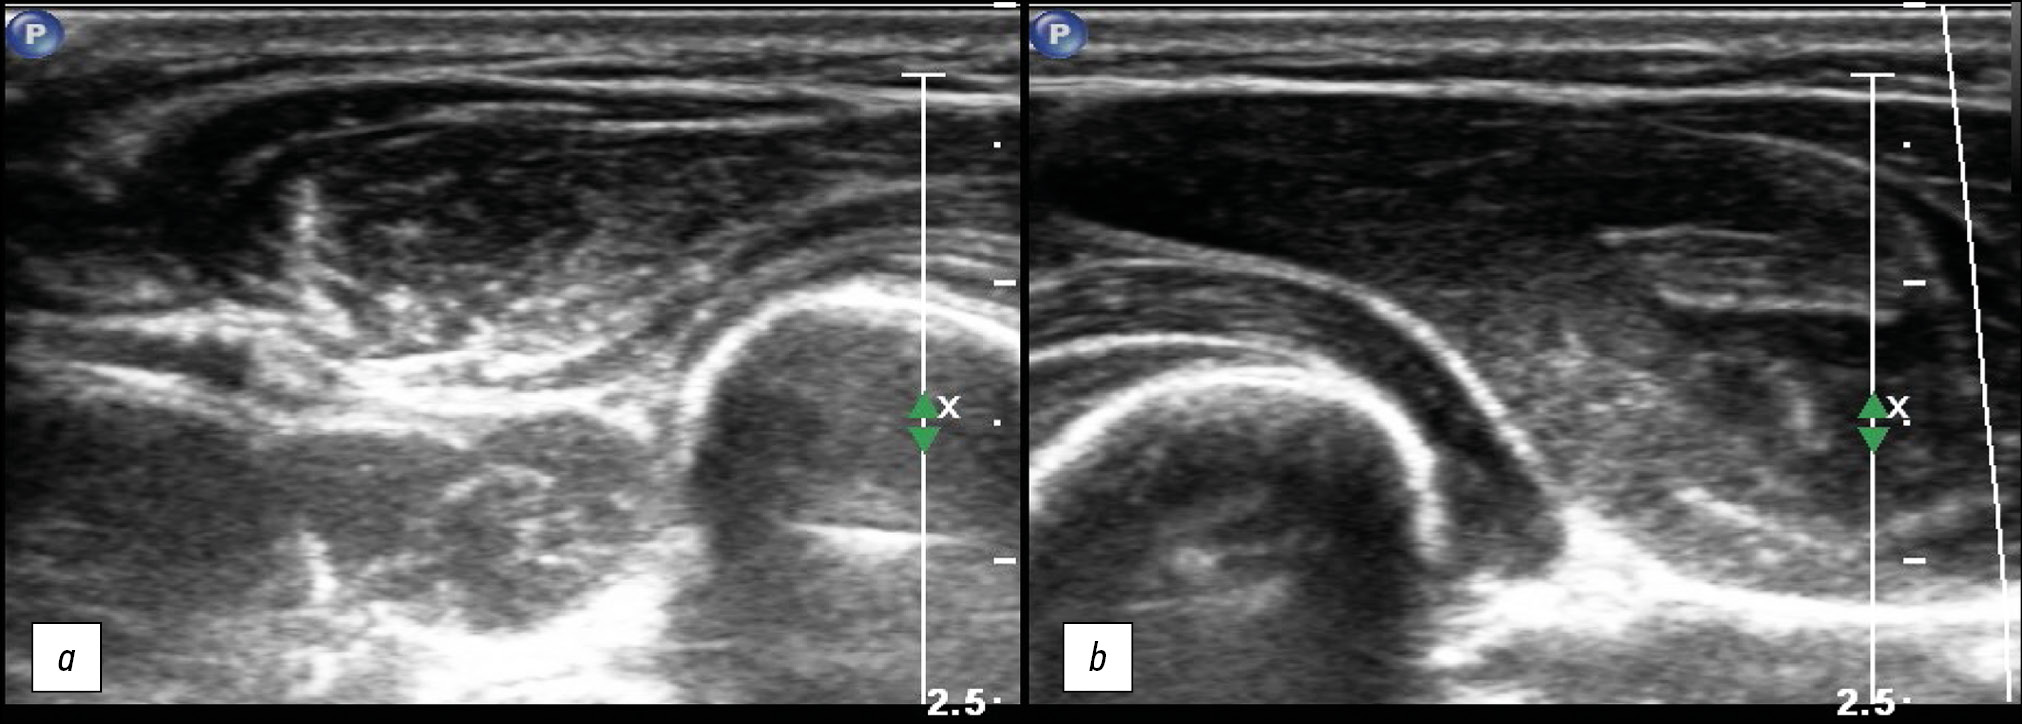

In polyneuropathies, including autoimmune neuropathies, nonspecific changes in the structure of peripheral nerves are also detected; an example is nerve thickening caused by thickening of nerve fibers in the composition of the nerve trunk, and a decrease in echogenicity. At the same time, differentiation into fibers and the clarity of the nerve contours are preserved (Fig. 8).

Fig. 8. Ultrasound examination of the tibial nerve in a patient with disimmune neuropathy illustrating nonspecific changes in the peripheral nerve structure. Transverse (a) and longitudinal (b) projections.